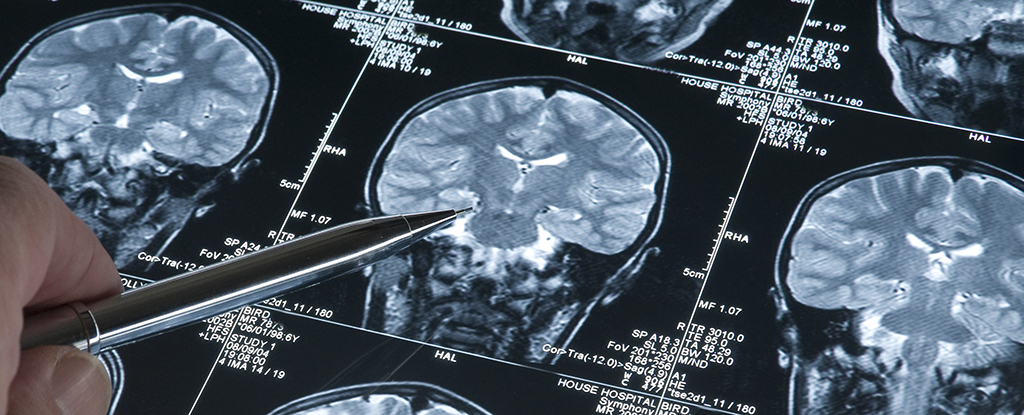

After accounting for factors such as age, sex, and some key health issues, the study found that those in poorer households showed more signs of white matter aging in their brains in MRI scans, and scored lower on cognitive tests than those in wealthier households.

Here, the team wanted to take a closer look at why that might be, finding that the number of fibers branching out from each neuron (neurite density) and the extent of protective coating on these fibers (myelination) seemed to be contributing to a more rapid breakdown in white matter.

This work detected how freely molecules – mostly water – move through the brain (mean diffusivity), which appears to be dependent on the amount of myelin and the density of neuron branches, indicating they are important factors to focus on.